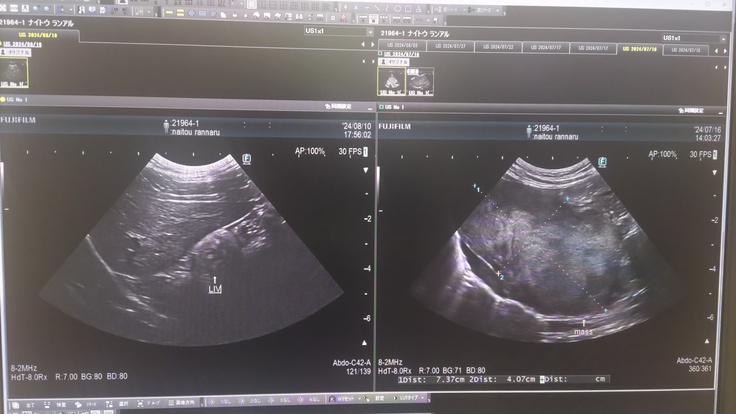

超音波検査で肝臓にも腫瘍が見つかったこと。恐らく胸のリンパ腫から転移したと思われるが、こちらも共に検査機関に送ったこと。

肝臓の腫瘍 約7cm×4cmの巨大腫瘍 写真中央の十字点線で示しているのが腫瘍です

左の写真が現在の肝臓の腫瘍(ほぼ無し)、

右の写真が7/15の時の腫瘍(7cm×4cm)